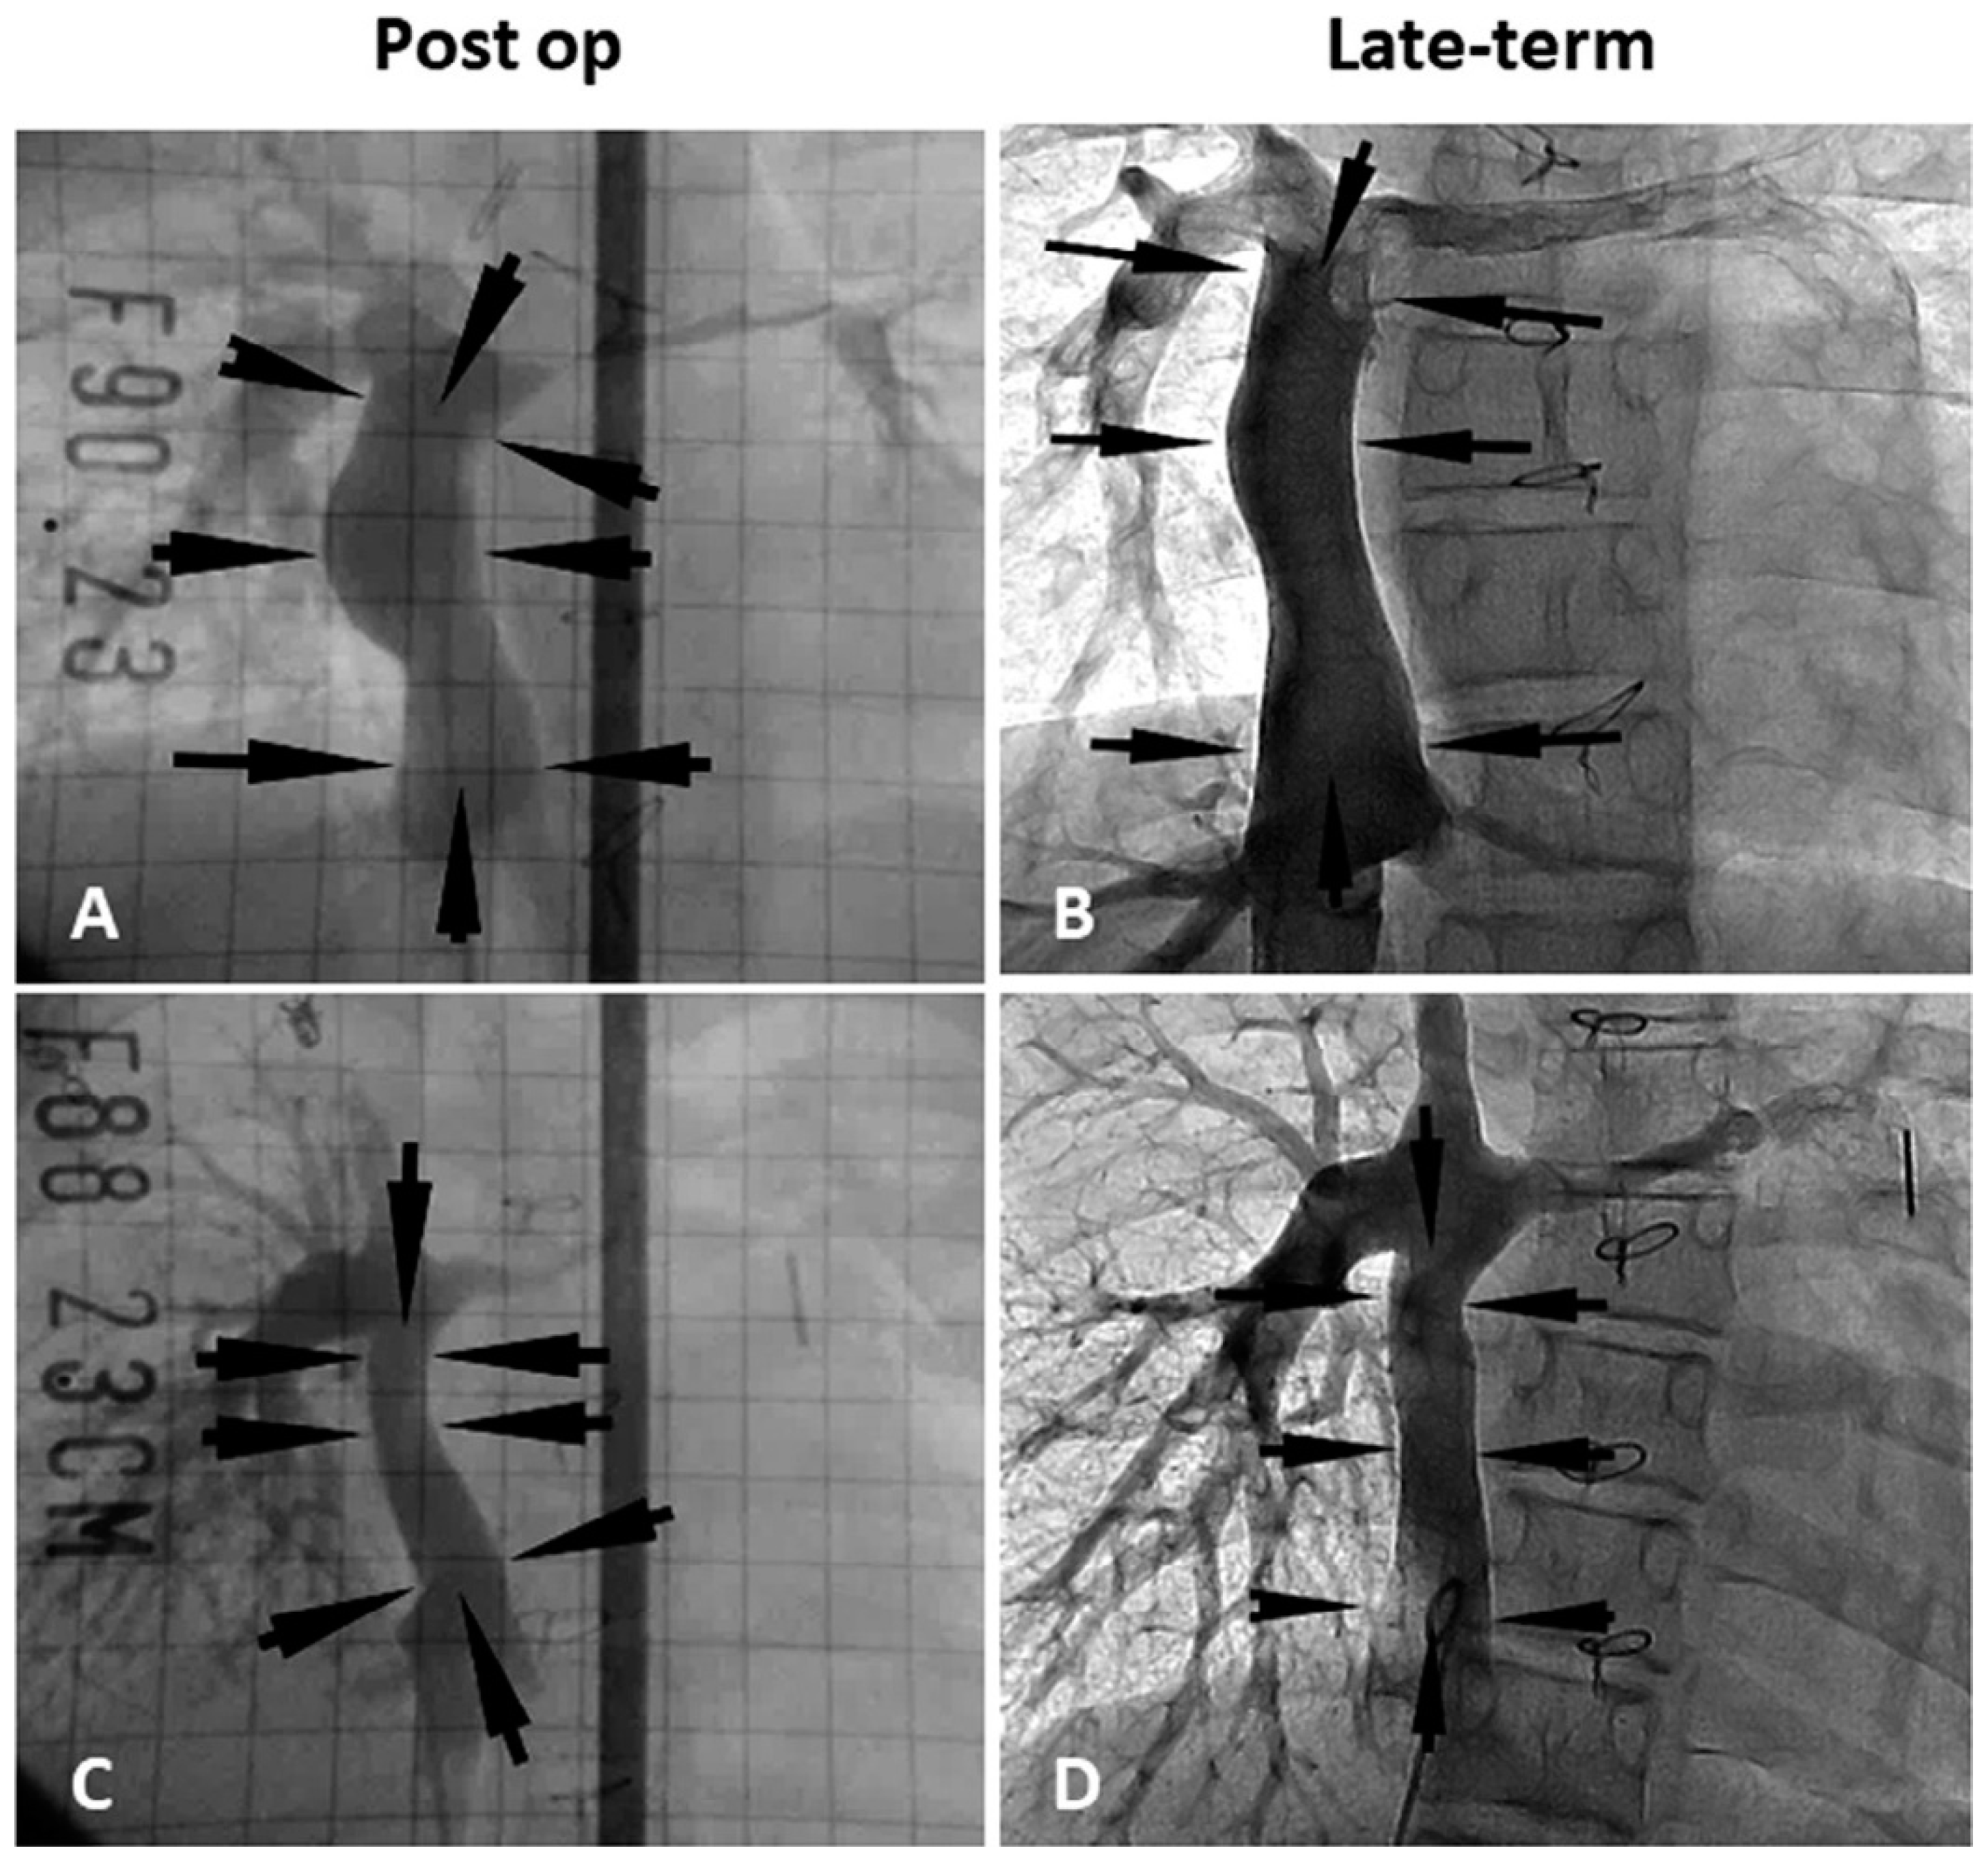

3. Clinical Study in Venous Model

- Shinoka, T.; Imai, Y.; Ikada, Y. Transplantation of a tissue-engineered pulmonary artery. N. Engl. J. Med. 2001, 344, 532–533. [Google Scholar] [CrossRef] [PubMed]

- Shinoka, T.; Matsumura, G.; Hibino, N.; Naito, Y.; Watanabe, W.; Konuma, T.; Sakamoto, T.; Nagatsu, M.; Kurosawa, H. Midterm clinical result of tissue-engineered vascular autografts seeded with autologous bone marrow cells. J. Thorac. Cardiovasc. Surg. 2005, 129, 1330–1338. [Google Scholar] [CrossRef] [PubMed] [Green Version]

- Hibino, N.; McGillicuddy, E.; Matsumura, G.; Ichihara, Y.; Naito, Y.; Breuer, C.K.; Shinoka, T. Late-term results of tissue- engineered vascular grafts in humans. J. Thorac. Cardiovasc. Surg. 2010, 139, 431–436. [Google Scholar] [CrossRef] [PubMed]

- Sugiura, T.; Matsumura, G.; Miyamoto, S.; Miyachi, H.; Breuer, C.K.; Shinoka, T. Tissue-engineered Vascular Grafts in Children With Congenital Heart Disease: Intermediate Term Follow-up. Semin. Thoracic. Surg. 2018, 30, 175–179. [Google Scholar] [CrossRef] [PubMed]